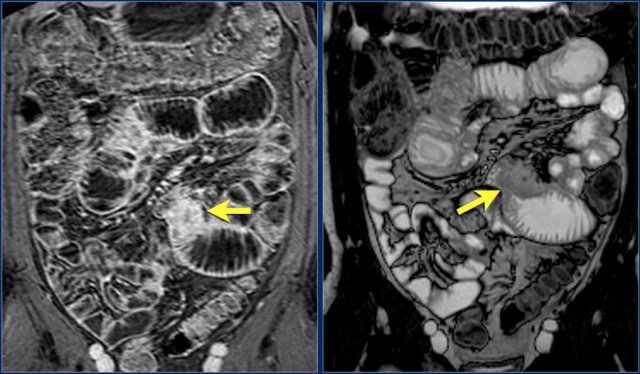

The findings are:

- Reversed fold pattern indicating celiac disease

- Ileal-ileal intussusception (yellow arrow), in a patient with multifocal small bowel lymphoma (not all lesions shown here).

- Mesenteric lymphadenopathy (red arrows).